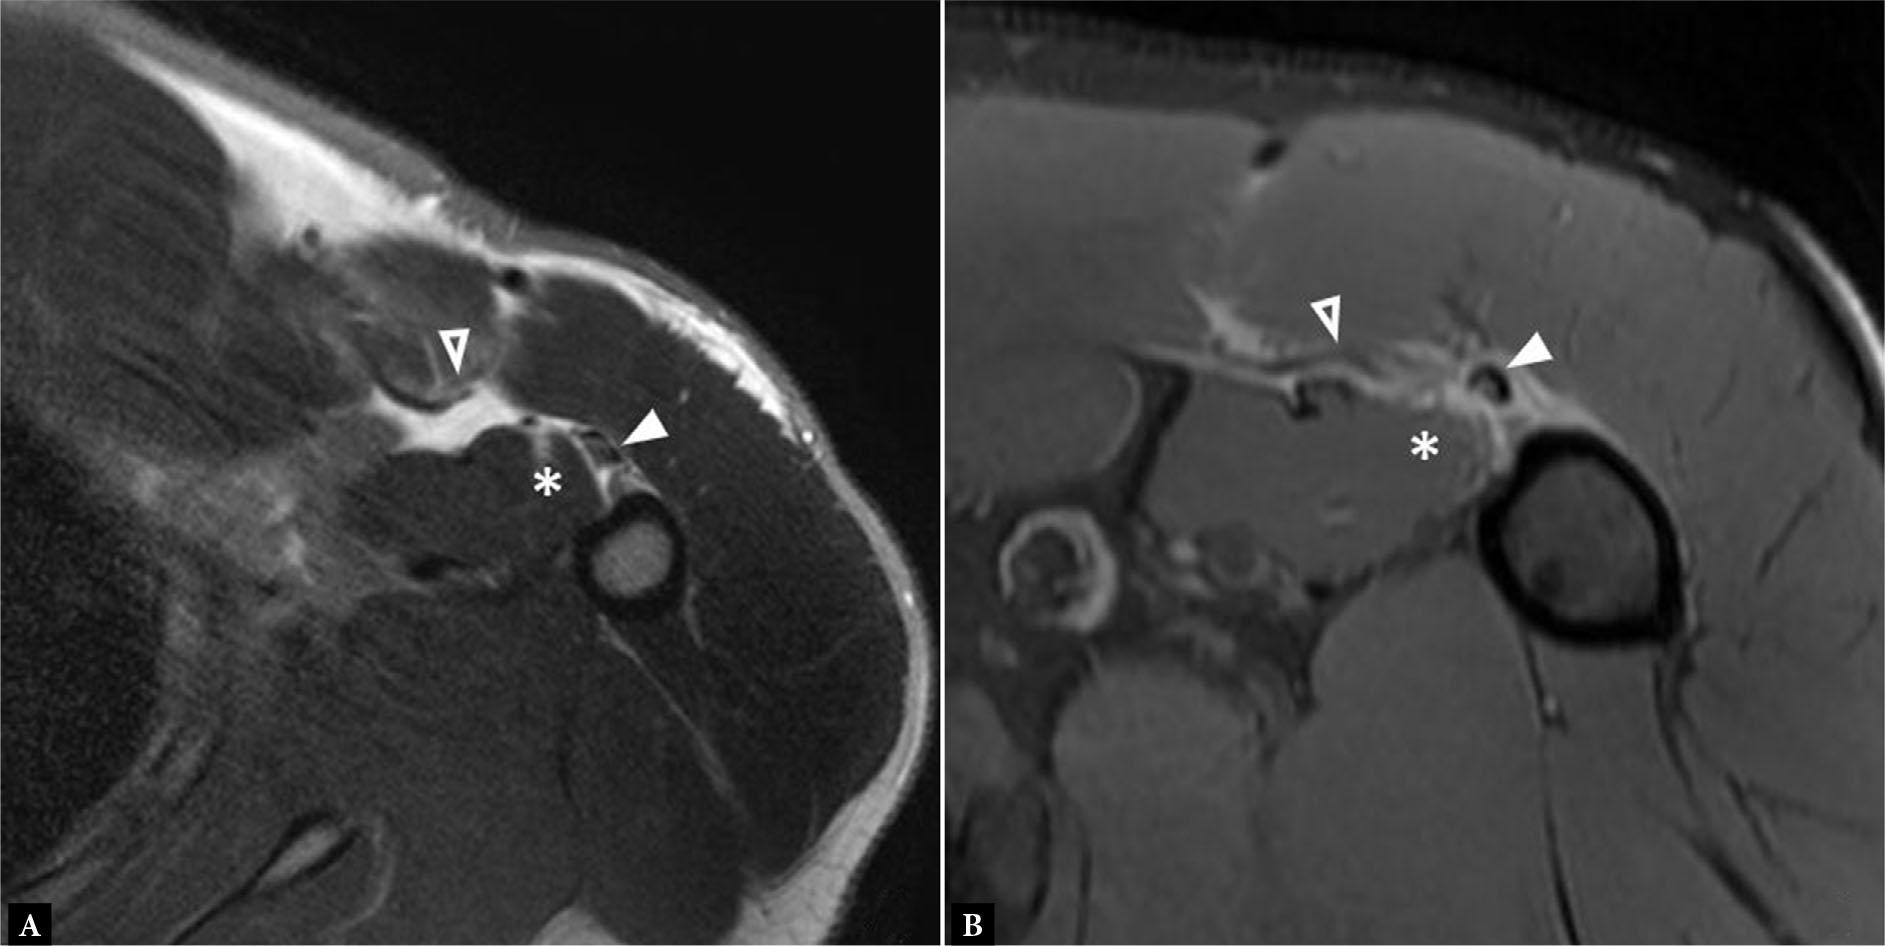

Fig. 10.

A, B. Consecutive axial fluid-sensitive MR images in a patient who previously underwent PM tendon repair show a full width partial thickness re-tear of the PM tendon. The superficial anterior layer is torn and retracted (B, empty arrowhead) with adjacent hematoma formation (A,B-asterisk) while the deep posterior layer is thickened but intact (A,B – solid arrowheads). Note the susceptibility artifact from surgical hardware (arrow, A). C. Long axis gray scale ultrasound image in a different patient shows an anechoic linear tear in the sternal head, measuring approximately 3 cm superior to inferior (arrows). D. Long axis gray scale ultrasound image further laterally at the PM tendon insertion in the same patient shows the intact superficial anterior tendon layer (arrowheads) and avulsed deep posterior layer with accompanying mineralized periosteum (arrow); bicipital groove is shown for reference (asterisk)